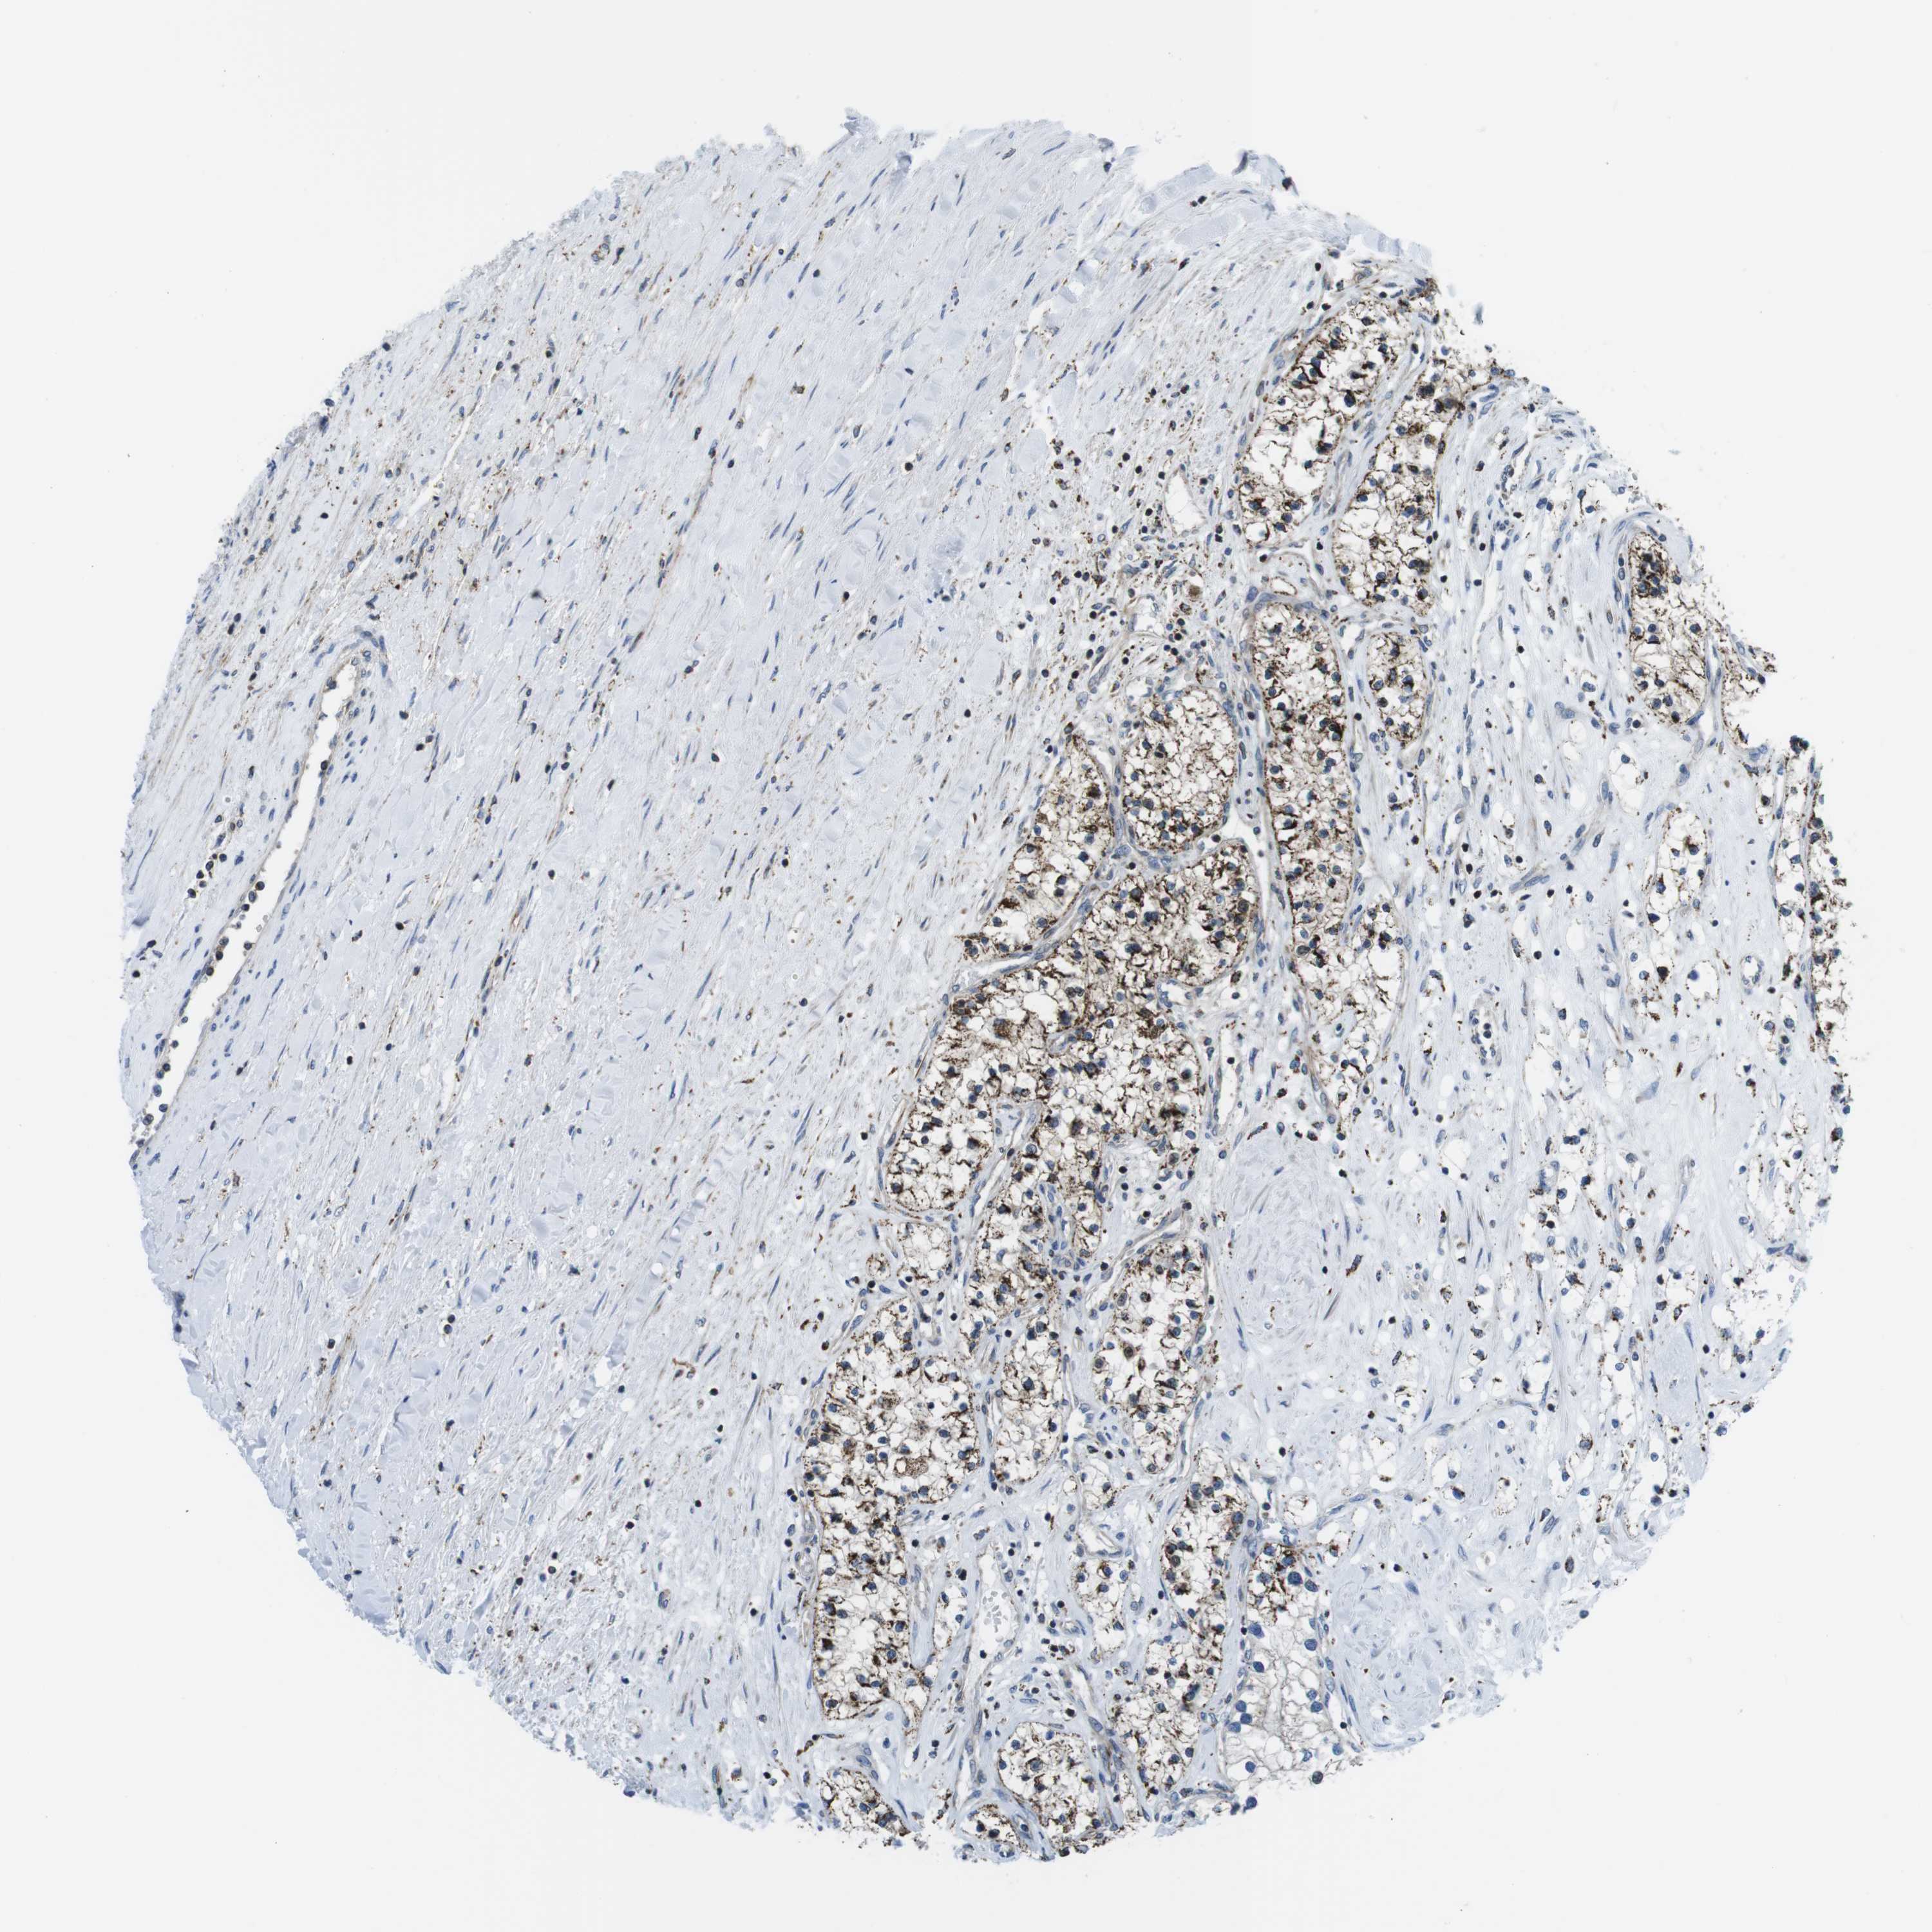

KCNE3 is potential prognostic, high expression is favorable in Kidney Renal Clear Cell Carcinoma (validation)

: 91.82